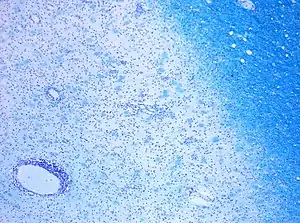

| CD68-stained tissue shows several macrophages in the area of a demyelinated lesion caused by MS. | |